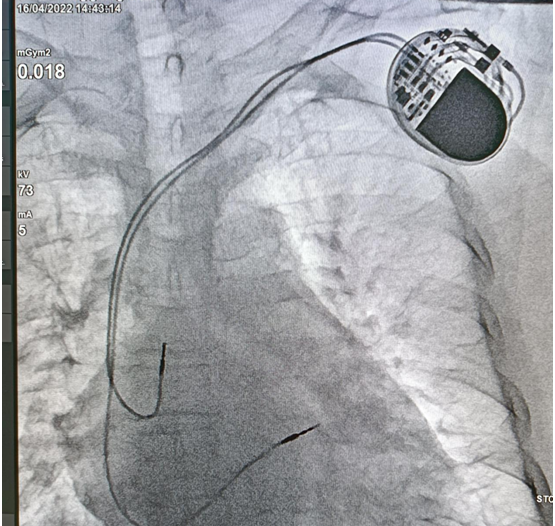

心脏起搏器植入术

心脏起搏器植入术是指人工植入心脏起搏器,用特定频率的脉冲电流,经过导线和电极刺激心脏,代替心脏的起搏点带动心脏搏动的治疗方法,是治疗不可逆的心脏起搏传导功能障碍的安全有效方法,特别是治疗重症慢性心律失常。

心脏起搏器早期主要治疗缓慢心律失常,如病窦房结综合征(严重窦性心动过缓、窦房传导阻滞、窦性静止、心动过缓过速综合征)、房室传导阻滞(高度或完全性及二度II房室传导阻滞、持续或间歇性室内三分支传导阻滞或有症状的室内二支传导阻滞者)等,随着起搏技术的发展,起搏器治疗范围进一步扩大,目前起搏器治疗肥厚梗阻型心肌病、三腔起搏器(CRT)治疗扩张型心肌充血性心衰、埋藏式自动复律除颤仪(ICD)治疗顽固性快速心律失常都具用很好的临床疗效。

自2011年以来,我院心病科采用安装双腔、三腔(CRT)及植入式心脏自动除颤复律起搏器(ICD),为心动过缓、传导阻滞、心动过速及心力衰竭的患者解除疾苦,也为难治性心力衰竭和反复发作危及生命的室性心动过速、室颤患者提供了新的治疗途径。

植入后的心脏起搏器